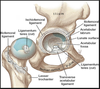

ligament of head of the femur

aka ligamentum teres